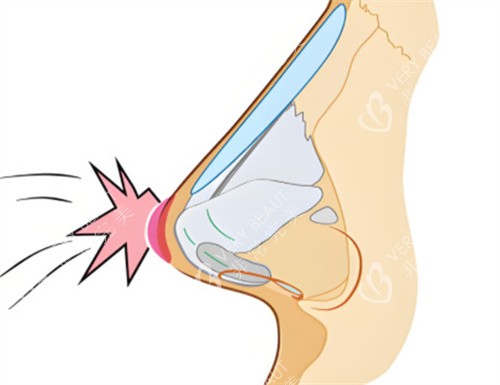

张医生拿个小探头在我鼻梁上扫了扫,说:“你这是假体层次放浅了才透光,鼻头歪是因为缝合时固定点没对齐,不用重做假体,把假体往深了调,再重新固定鼻头就行,还能保留你之前的鼻型基础,修复更快。”没有夸大结果,全是实实在在的分析。